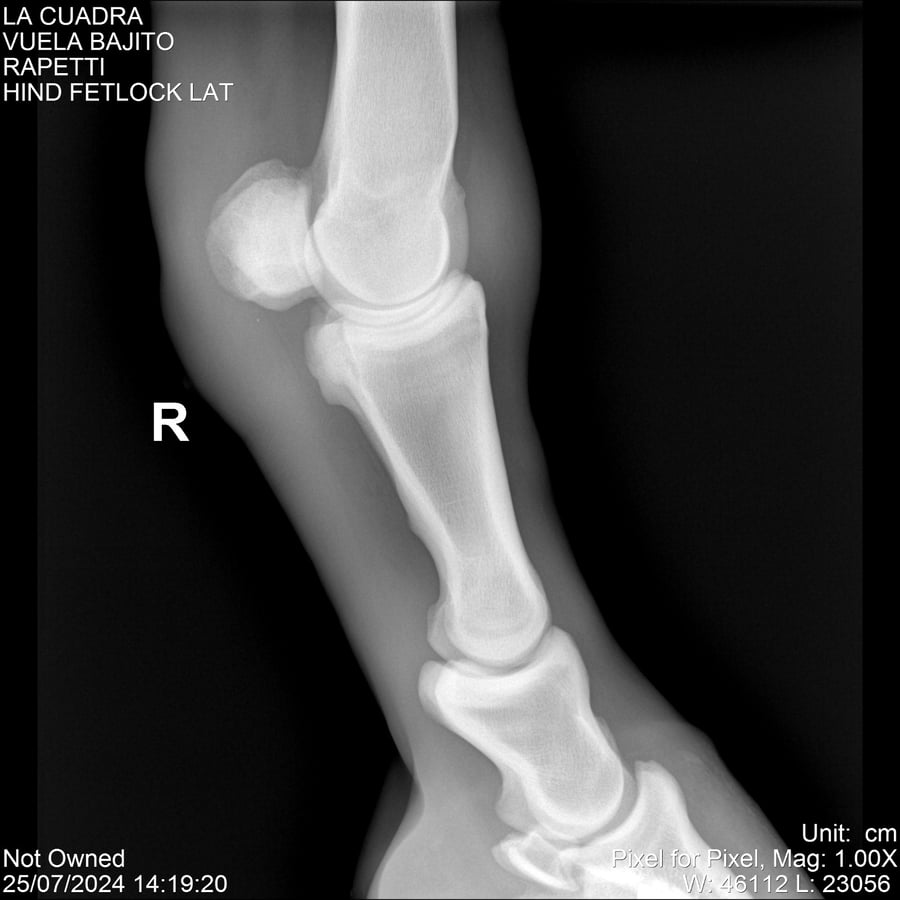

LOTE 16, VUELA BAJITO Lote Anterior Volver al remate Lote Siguiente Ficha Contacto Montevideo - Ficha del Lote Identificador: #284451 Categoría: Yeguarizos Montevideo - 77 Visualizaciones ClicData Contacto Empresa: Abelenda N. R., Walter Hugo Nombre*: Teléfono* : E-mail* : Mensaje Enviar Registrese gratis Este contenido Exclusivo está disponible sólo para usuarios registrados Ingresar